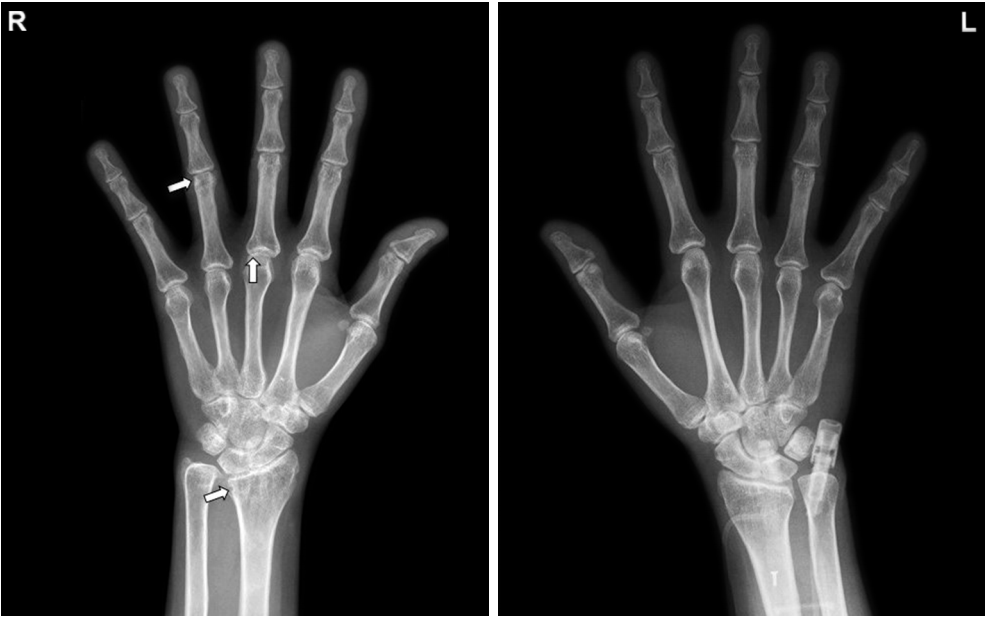

患者在甲氨蝶呤15 mg/周、泼尼松龙5 mg/d、柳氮磺吡啶 2 g/d治疗下,仍有难治性RA活动。常规x线光片显示右腕关节、近端指间关节和掌指关节区骨侵蚀,腕关节间隙变窄(图1)。

图1 常规x光片显示右手腕、第4指间关节近端和第3掌指关节侵蚀(白色箭头),手腕关节间隙变窄。